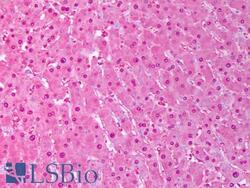

Supportive validation

- Submitted by

- LSBio (provider)

- Enhanced method

- Genetic validation

- Main image

- Experimental details

- Anti-SOD1 antibody IHC of human liver, hephatocytes. Immunohistochemistry of formalin-fixed, paraffin-embedded tissue after heat-induced antigen retrieval. Antibody concentration 10 ug/ml. This image was taken for the unconjugated form of this product. Other forms have not been tested.